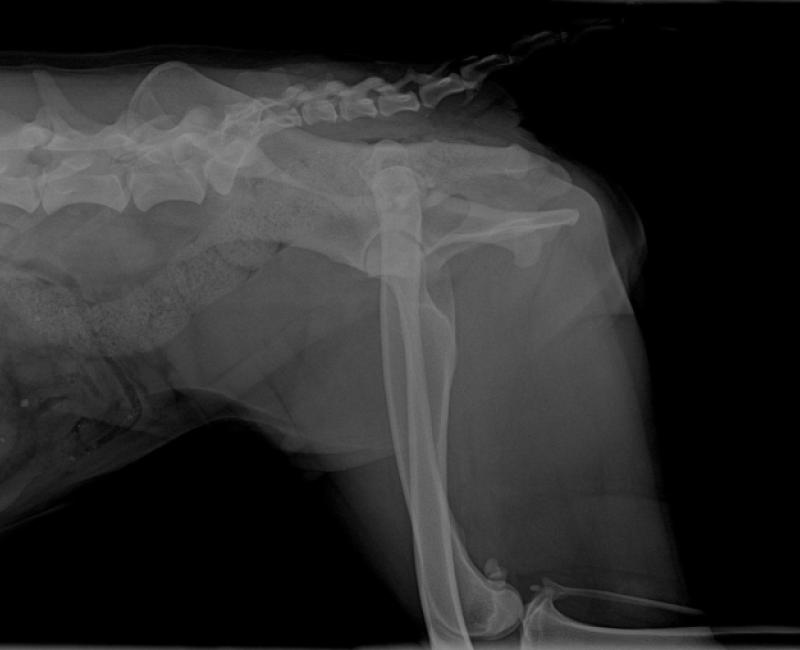

Tanto que ha sucedido lo peor: golpeada por un coche fracturándole el fémur. Es jovencita, un año y medio, de bello pelaje y maravilloso carácter. Se ha dejado hacer las radiografías sin rechistar y, a pesar del dolor que debe tener, te muestra la pancita alegremente. Es noble, obediente y muy amigable con todo el mundo. También superó un envenenamiento que la dejó muy delgada y tardó en recuperar la fuerza. Dispone de 1 sucio cortijo que le "presta" uno de los agricultores para dormir y todos los vecinos de la zona le ponemos alimento pero nadie la cuida bien. Necesita ser operada de su pata y que se recupere en un lugar limpio y seguro. Me niego a que siga sufriendo, merece un hogar.

Obviamente ambos ya están rescatados: Mauro en el refugio y Emilia en una casa de acogida recuperándose de su operación, ya que aunque la señora ha tenido toda la buena fe y se ha gastado su buen dinero sus veterinarios solo han hecho una chapuza tras otra, vendando sobre vendajes anteriores, los cuales al levantar nuestras veterinarias la carne estaba podrida y la única solución ha sido amputar. Pero ella está totalmente feliz!!!!!.